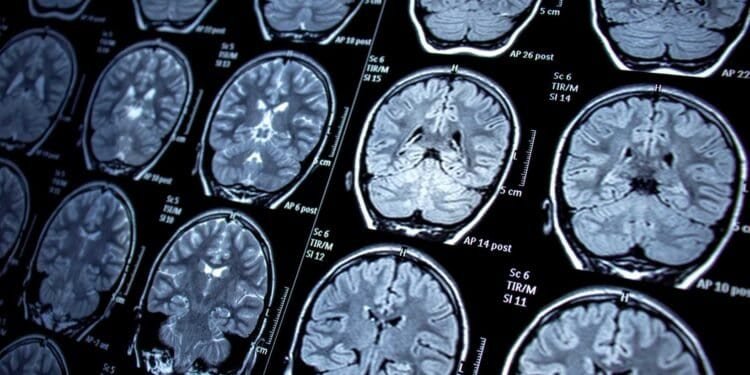

Mold-related brain infections are rare but can be life-threatening. Diagnosis typically involves a combination of imaging tests, such as CT scans and MRIs, and laboratory tests, such as fungal cultures and serological tests. Treatment typically involves antifungal medications, such as amphotericin B and voriconazole, and may require hospitalization.